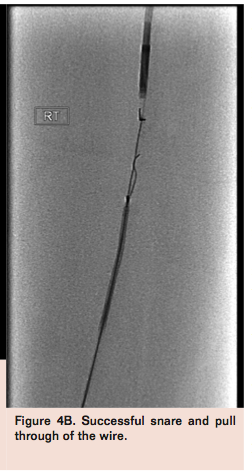

Re-entry device, snare positioning, deployment and “flossing”

If re-entry from the retrograde sheath fails, the re-entry and snare technique is useful to gain “through and through” luminal access. From the antegrade sheath, position the Outback catheter as distally as possible in the subintimal plane (usually at the point of failed re-entry) (Figure 4A). From the retrograde sheath, advance a catheter and snare as proximally as possible. Deploy the Outback needle and advance the wire from the Outback catheter into the snare and pull the snare through the retrograde sheath (Figure 4B). Fluoroscopy in multiple planes helps to align the puncture towards the snare and reduce the number of passes needed for success. If there is particularly dense calcification at the initially selected re-entry site, then a more proximal or distal position should be tried.